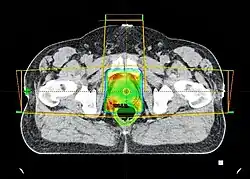

Przykładowy układ wiązek promieniowania i rekonstrukcja kości miednicy w Radioterapii nowotworu gruczołu krokowego

Przekrój z badania (tomografi komputerowej) CT z dawką promieniowania, przykładowy układ wiązek promieniowania w radioterapii nowotworu gruczołu krokowego (prostaty)